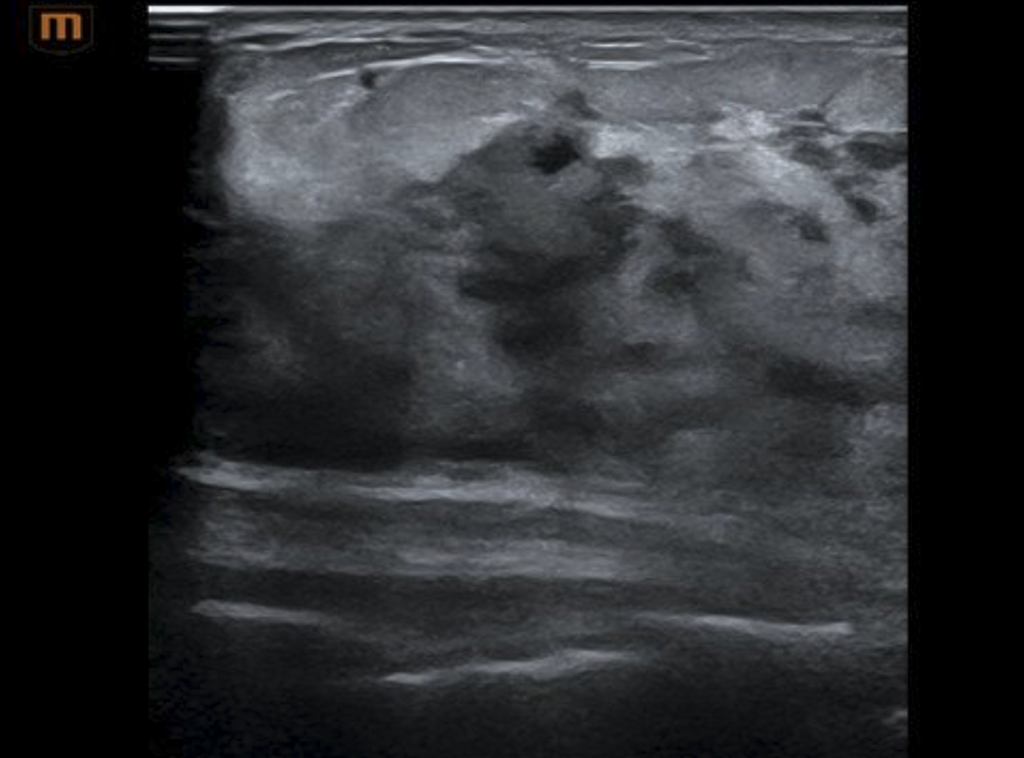

此时的乳腺组织致密、血流丰富、内部结构乱七八糟。肿瘤藏在里面,就像暴雨天在一堆灰色乌云里找一片颜色只深一丢丢的乌云——探头扫过去,很容易觉得“还行,挺正常的”。

中国数据显示,80%的妊娠期和哺乳期乳腺癌确诊时已经发生淋巴结转移。不是B超没用,是这时期的乳房需要更综合的判断——手摸、眼看、必要时的穿刺,一样不能少。

尤其在哺乳期这种“真假难辨”的背景下,穿刺是唯一的“终审法官”。肉眼看到的是脓,显微镜下才能看见癌。